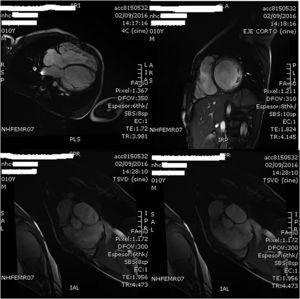

A los 11 años el paciente sufre un nuevo ingreso hospitalario por descompensación grave de su insuficiencia cardiaca que obliga a su internamiento en la unidad de cuidados intensivos pediátricos (UCIP), detectándose ecocardiográficamente la grave disfunción del VI y la dilatación severa del VD, ya conocida (fig. 3). A pesar de la intensificación del tratamiento médico asociando soporte inotrópico, el paciente perpetuó su cuadro franco de bajo gasto con deterioro de la función renal y hepática, por lo que, tras evaluación en sesión multidisciplinar, se consideró al paciente candidato con carácter urgente al implante de una asistencia ventricular izquierda junto a la valvulación del tracto de salida ventricular derecha (TSVD) mediante una bioprótesis valvular en posición pulmonar.

Con este razonamiento se llevó a cabo el implante de una bioprótesis en posición pulmonar asociado a una asistencia ventricular izquierda exclusiva, con buen resultado hemodinámico (fig. 5) que permitió precargar adecuadamente el VI asistido a pesar de disfunción del VD (FE del 34% en cardio-RMN de 2 años antes) sin necesidad de implantar una asistencia derecha, lo que se tradujo en una franca mejoría del gasto cardiaco y la rápida normalización de la función renal y hepática que permitió listar precozmente como urgencia cero para trasplante cardiaco a nuestro paciente.